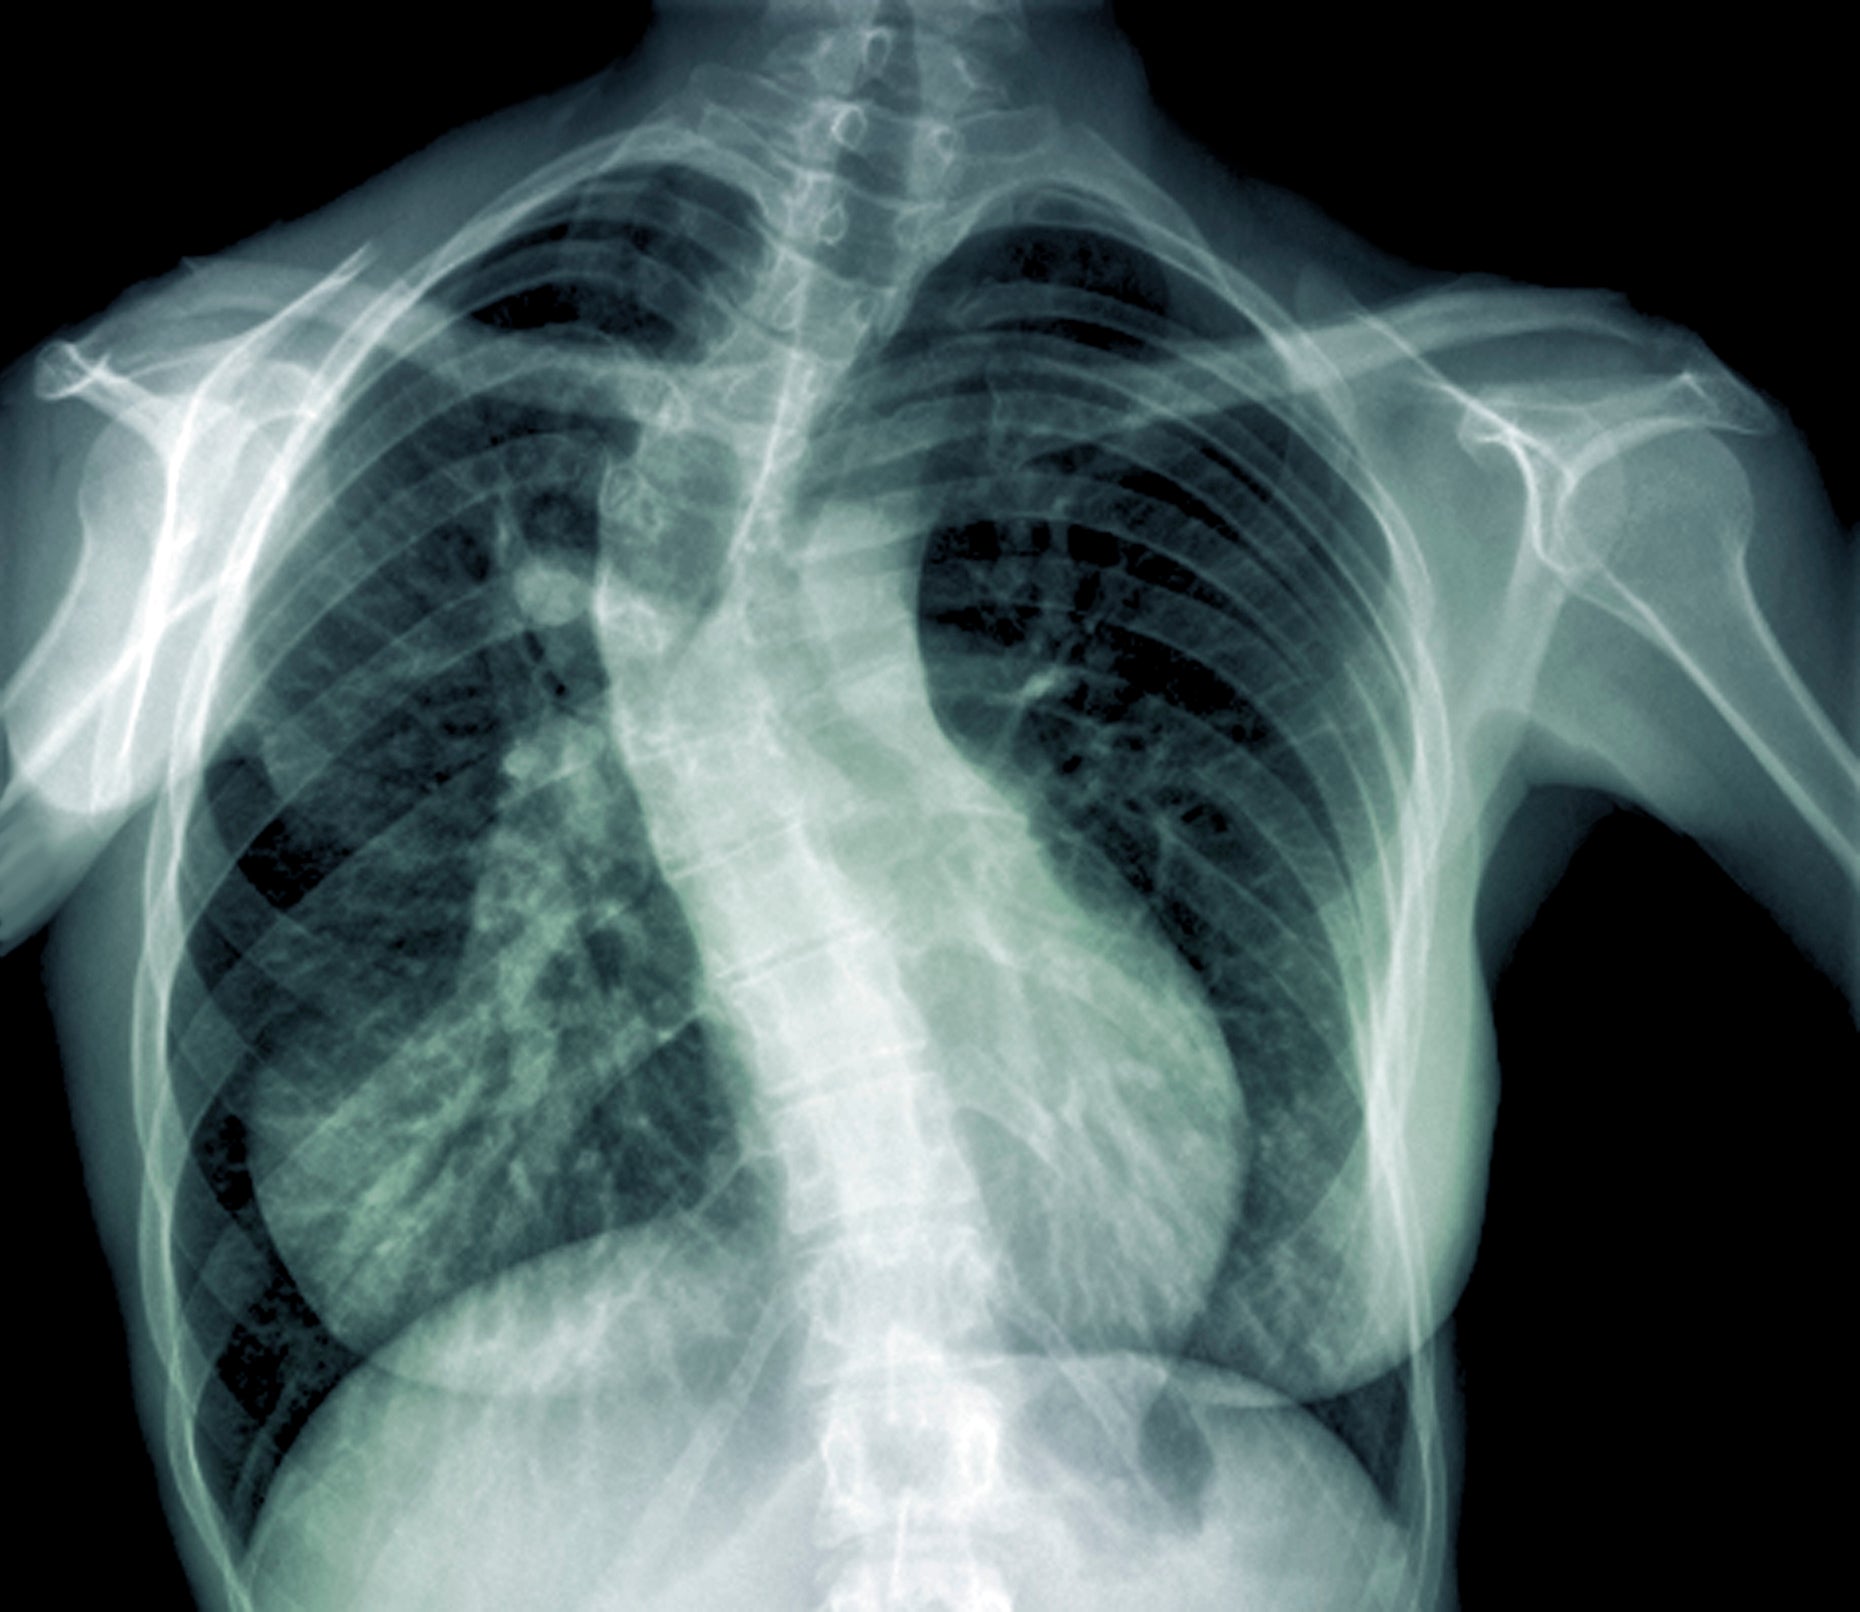

What is scoliosis?

It’s really just an abnormal curve of the spine. It’s fairly common, and approximately 3% of children are diagnosed with a mild or small curve (greater than 10 degrees). Only 0.3% progress to having a much bigger curve (greater than 30 degrees).